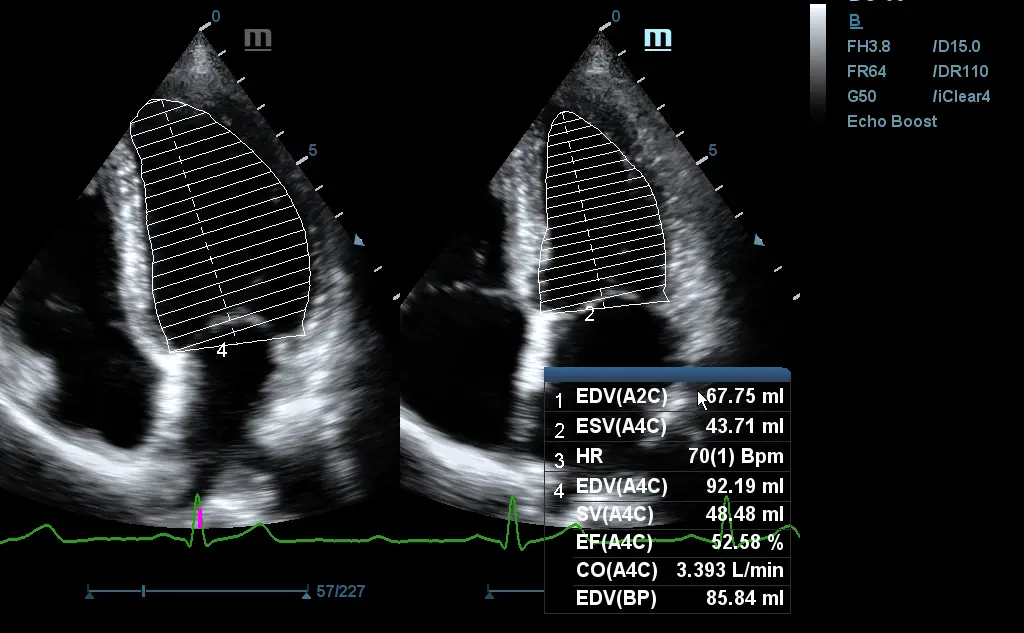

Auto EF (опция)

Интелигентен начин за анализ на 2D ехо клипове за автоматично разпознаване на диастолa / систолa и изходни EDV / ESV / EF и др. Резултати чрез метода на Симпсън.

Измерване в B режим

Измерване в Doppler режим